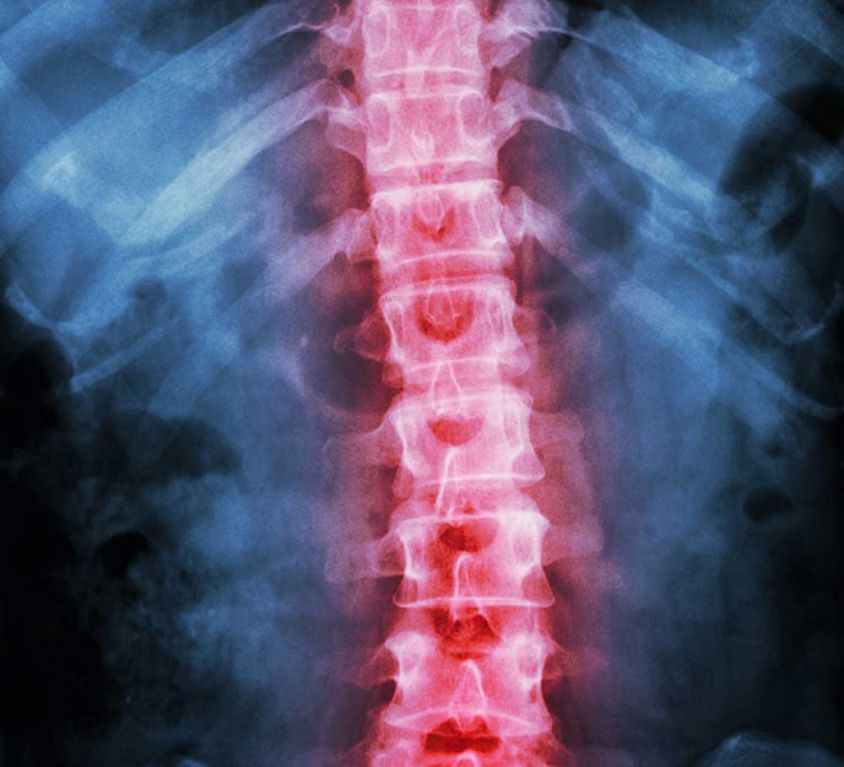

Spine Procedures

We specialize in the professional diagnosis and treatment of back pain and diseases of the spinal column. The main goal is to treat each individual patient for his back pain, his spinal disk problems or his spine disease as effectively and safely as possible – conservatively as well surgically. Accordingly, we offer a broad range of services from minimally invasive and endoscopic techniques for treatment of herniated disks to their artificial replacement to sometimes stiffening of the spinal vertebrae.

The most common reasons for acute lower back pain are a herniated disk or the degeneration of the spinal disk itself. Our doctors have carried out hundreds of successful endoscopic surgeries. Similarly, the most common reason for acute neck pain is also a herniated disk.

Surgical treatment is offered for spinal stenoses, spondylolisthesis and other degenerative, traumatic or inflammatory diseases of the cervical, thoracic and lumbar spine and – if necessary – even the insertion of an artificial disc replacement.